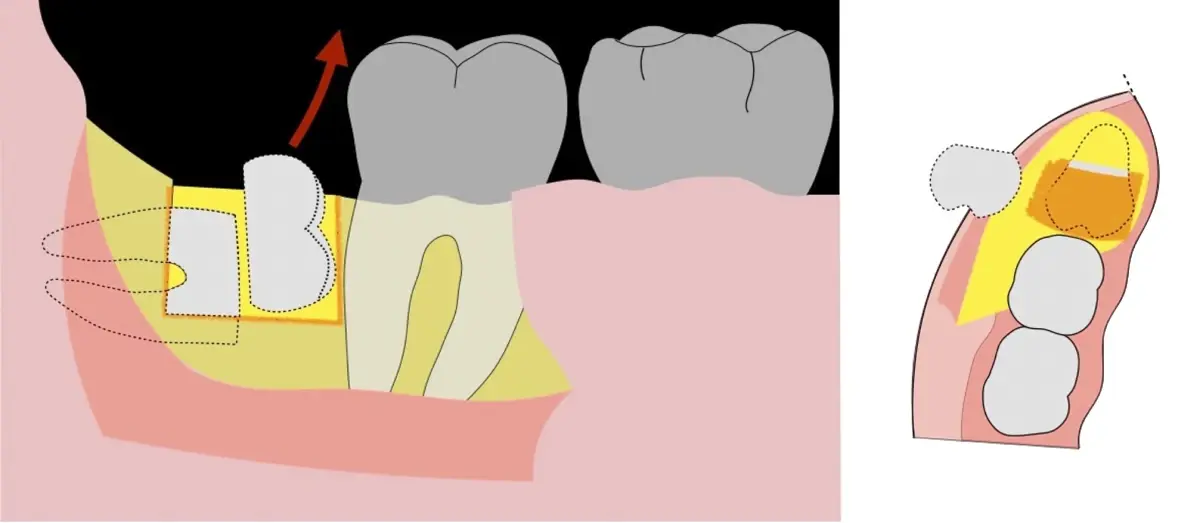

El procedimiento puede variar en su complejidad dependiendo de su ubicación, profundidad, angulación, y la densidad ósea circundante.2 Uno de los pasos más críticos y cruciales en la extracción es la osteotomía previa y concomitante al acceso quirúrgico del diente, para lo cual se utilizan diversos instrumentos como cinceles y martillos, instrumental rotatorio o de corte por ultrasonido.3

El instrumento piezoeléctrico utiliza un corte micrométrico que retira un área de superficie mínima de hueso, y reduce el riesgo de termonecrosis marginal en comparación con las fresas rotatorias convencionales.

En contraste, el instrumento piezoeléctrico utiliza un corte micrométrico que retira un área de superficie mínima de hueso, y reduce el riesgo de termonecrosis marginal en comparación con las fresas rotatorias convencionales.9 Los micromovimientos mejoran la precisión en el corte y el control táctil, y eliminan las macrovibraciones que se producen con los instrumentos rotatorios.10 Su frecuencia de oscilación es la amplitud de 60-200 μm horizontalmente y de 20-60 μm en sentido vertical, lo que es muy inferior en comparación con las micro sierras oscilantes; por lo tanto, proporciona cortes de osteotomía precisos y seguros. Adicionalmente, posee vibraciones ultrasónicas que descomponen el líquido de irrigación en partículas muy pequeñas (fenómeno de cavitación, que produce un efecto hemostático y así reduce la pérdida de sangre), lo que proporciona una visión clara y sin obstáculos del campo quirúrgico11,12.